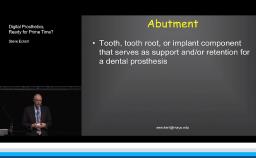

Steven Eckert

- Academy Author